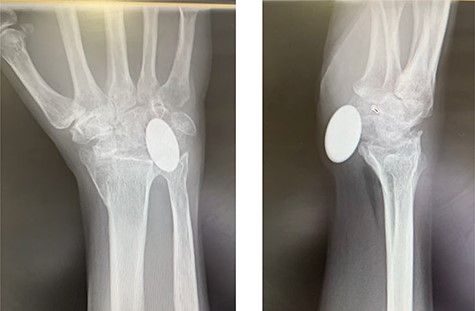

Radiographs demonstrated that the Pyrocarbon implant was palmarly displaced and rotated 90 degrees; it had migrated into the carpal tunnel/ distal forearm (Fig. 2). The clinical diagnosis was compression of the ulnar due to the migration of implant. Surgery was carried out 1 month later during which the Pyrocarbon Amandys wrist implant was removed through a volar approach (Fig. 3) and total wrist fusion was performed using a straight Arbeitsgemeinschaft für Osteosynthesefragen (AO) wrist fusion plate (Fig. 4). The surgery successfully relieved all wrist pain and was accompanied by prompt resolution of symptoms of ulnar nerve compression; she was discharged from follow-up approximately 3 months after surgery.

X-rays of the right hand showed palmar displacement of the pyrocarbon implant.